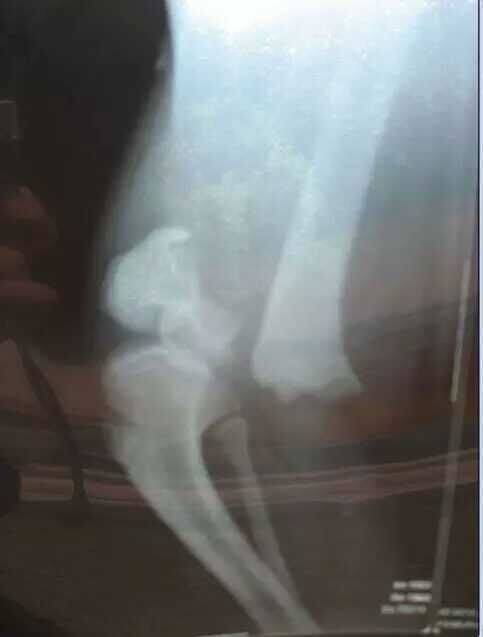

检查后专家发现,“缘小”的右后腿有明显的骨头错位,骺骨明显错开。随后的几次手法复位,都由于“缘小”的好动而失败了。2008年10月8日,“缘小”成功进行了骨科手术。为了用钛合金钢板对它复位后的断骨进行固定,专家们首先剃掉了它两只后腿的毛发,“扒裤照”也由此而来。